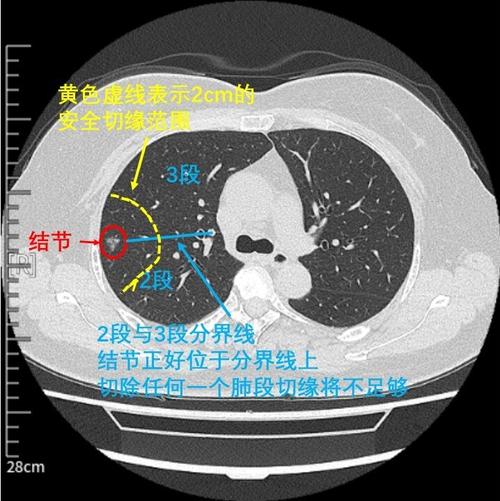

单孔胸腔镜右肺上叶 s2b s3a联合亚段切除术

难者不会会者不难之「庖丁解肺」丨一页手册·协和八